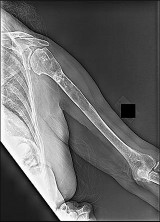

Figures 7a through 7d are the radiograph, MR images, and biopsy specimen of a 35-year-old man who has a painful, slowly enlarging knee mass. Which chromosomal translocation is characteristic of this pathology?

Synovial sarcoma is a soft-tissue sarcoma that usually occurs in young adults. Synovial sarcoma often causes pain, unlike most soft-tissue sarcomas, which generally do not cause pain. Imaging characteristics include soft-tissue calcifications on plain radiographs and a heterogeneous mass that is generally isointense to muscle on T1-weighted images and hyperintense to muscle on T2-weighted images. There are biphasic and monophasic types of synovial sarcoma. The biphasic

type, which is depicted here, has both spindle cell and epithelial components and will stain for both vimentin and cytokeratin. More than 90% of patients with synovial sarcoma have a characteristic genetic translocation of t(X;18), which results in the fusion protein SS18-SSX. This translocation can be stained for use of florescence in situ hybridization technology. t(11;12) is seen in Ewing sarcoma. T(9;22) is seen in extraskeletal myxoid chondrosarcoma. t(12;16) is seen in myxoid liposarcoma.